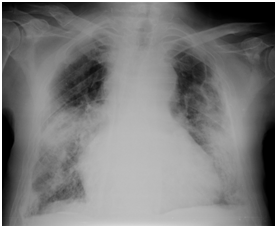

His blood counts showed anemia (hemoglobin 8.6 g/dL) and normal leukocyte and platelet levels. His laboratory investigations showed normal liver and renal enzymes, elevated C-reactive protein (58.44 mg/L, reference value <5 mg/L) and elevated sedimentation rate (121 mm/h). He had elevated folic acid (>20 ng/mL) and B12 vitamin (>2000 pmol/L) with low iron (36 ug/dL, reference value: 61-157 ug/dL) and normal ferritin and transferrin values. His thyroid tests were normal and his proBNP was high (3285 pg/mL, reference value < 300 pg/mL). His total proteins were normal (7.6 g/L) with low albumin (2.9 g/dL, reference value: 3.4-4.8 g/dL) and high β2-microglobulin (5150 ug/L, reference value: 800-2200 ug/L). He had an elevated immunoglobulin M (IgM) 4227 mg/dL (reference value: 40-230 mg/dL) with low IgA (63 mg/dL, reference value: 70-400 mg/dL) and IgG (507 mg/dL, reference value: 700-1600 mg/dL). His urinalysis showed more than 20 leukocytes per uL. His chest X ray revealed an enlarged heart silhouette, bilateral opacities and pleural calcifications compatible with asbestosis. (Figure 2) The cranial computerized tomography (CT) scan was normal for his age.

Figure 2 Chest X- ray showing an enlarged heart silhouette, bilateral opacities and pleural calcifications.